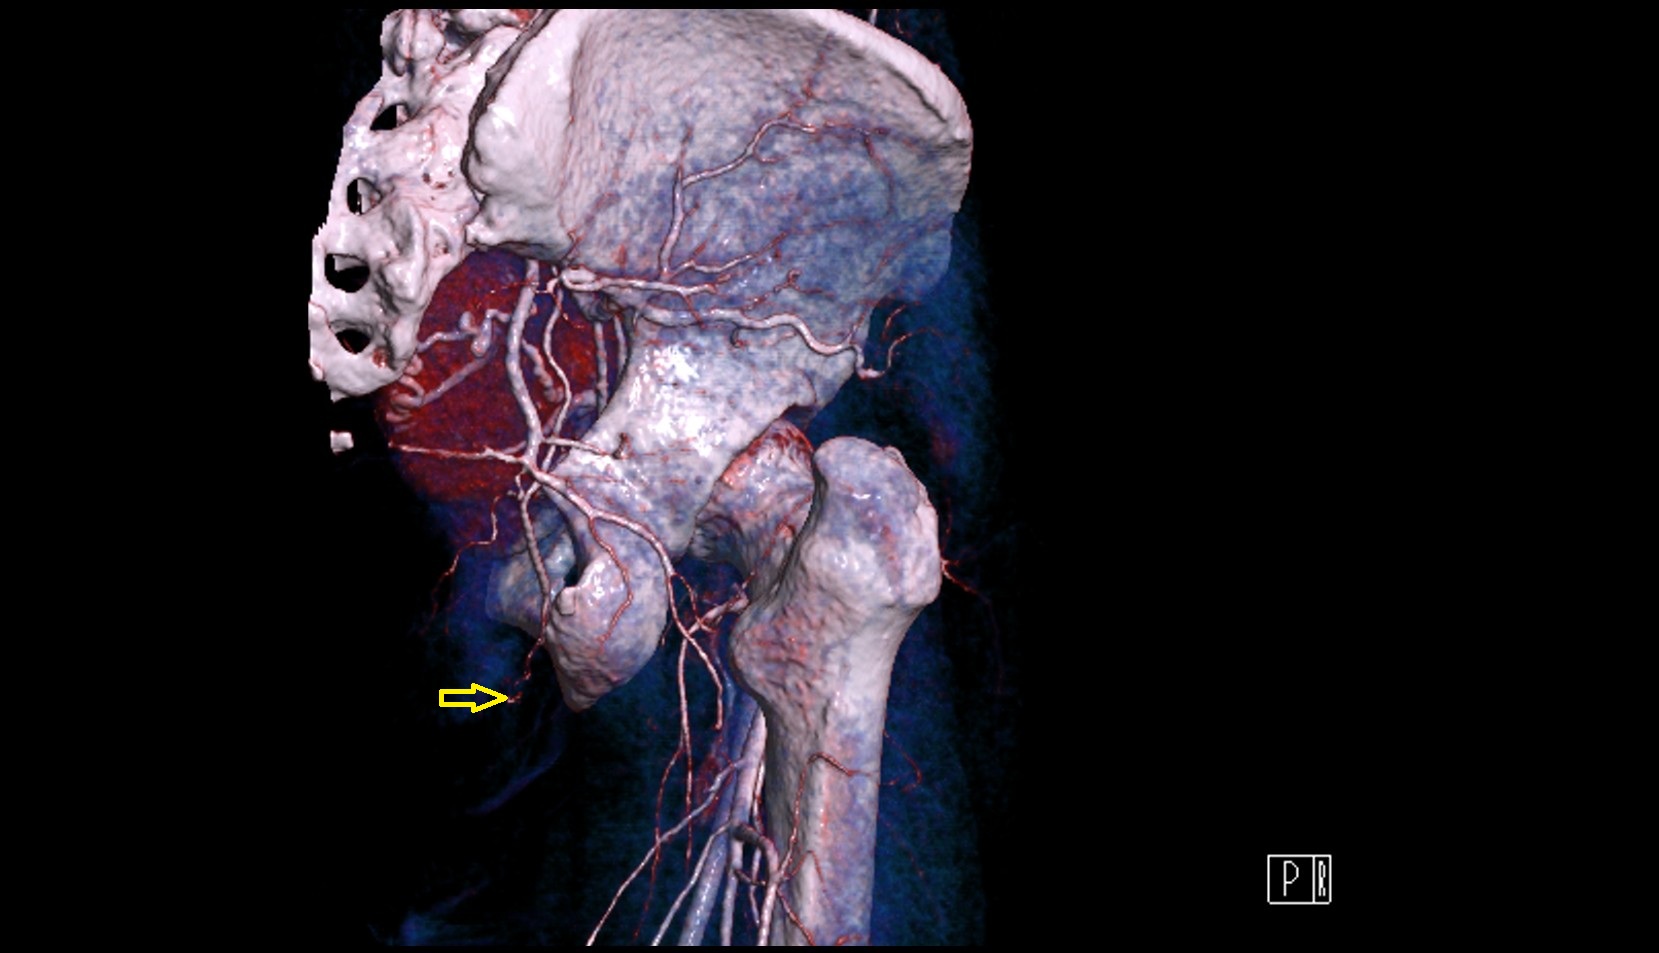

- External iliac artery

- Internal iliac artery

- Femoral artery

- Medial circumflex femoral artery

- Lateral circumflex femoral artery

- Deep femoral artery (profunda femoris)

- Obturator artery

- Superior gluteal artery

- Deep circumflex iliac artery

- Inferior gluteal artery

- common iliac artery

- Aortic bifurcation